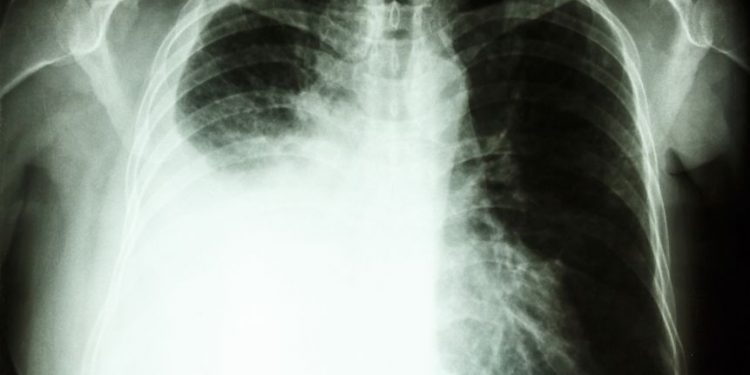

This is the most advanced stage of non-small cell lung cancer (NSCLC), also known as adenocarcinoma, when it has spread to one or more other parts of the body, notes the Moffitt Cancer Center in Florida. It may have spread to other areas within the chest, to other parts of the lungs or to distant regions of the body.

Stage 4 lung cancer has already metastasized to the other organs in the chest and elsewhere in the body. It can be classified in two substages, 4A and 4B. Stage 4A cancer is limited to the lungs, while stage 4B cancer has metastasized to other areas of the body, including the brain, bones, liver and adrenal glands.

The majority of patients with NSCLC at this stage have metastatic disease, meaning that the cancer has already spread from the lungs to other locations in the body, notes Moffitt. Patients with stage 4 metastatic NSCLC have a five-year survival rate of 8 percent. They are usually treated with platinum-based chemotherapy and radiation, as well as tyrosine kinase inhibitor target therapy or immunotherapy.